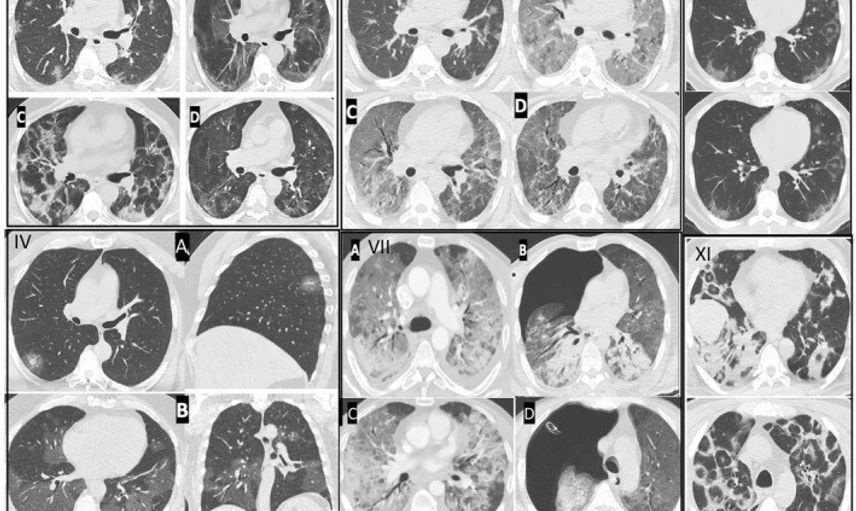

Kovid-19’un, özellikle kılcal damarlar üzerinde ciddi yaralar açtığını söyleyen Özkaya, "Pandemi sırasında takip ettiğimiz binlerce hastada, endotelit adı verilen damar iç yüzeyindeki hasarın ani ölümlere yol açtığını gözlemledik ve bu bulgularımızı uluslararası dergilerde paylaştık. Avrupa Kalp Dergisi’nin son verilerinde de Kovid-19 sonrası damar yaşlanmasının hızlandığı ifade edilmiştir" şeklinde konuştu.